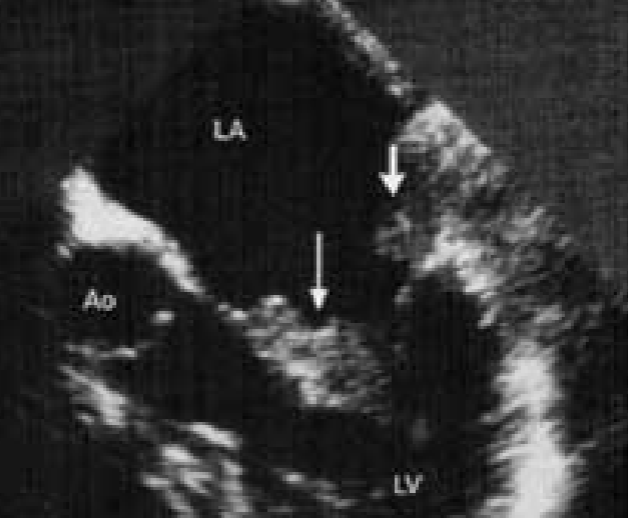

Lipomatous Hypertrophy of IAS

most common Lipoma location is IAS

“Dumbell” shaped IAS

d/t IAS thickening w/ sparing of fossa ovalis

may cause A-fib

associated w/ steroid use